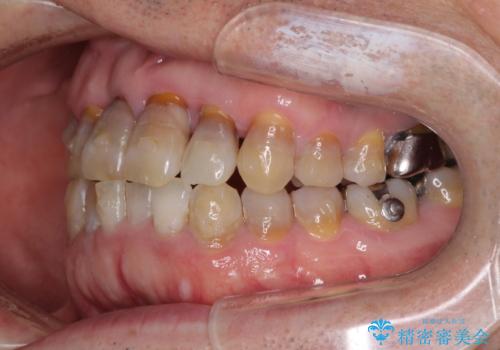

上顎の狭窄歯列 インビザラインによる拡大矯正

- 前歯の叢生と臼歯のクロスバイトを気にして来院された患者様です。

急速拡大装置による上顎の側方拡大を行い、その後はインビザラインより歯列を改善することとしました。

20代後半以降の男性は上顎骨の側方拡大処置の成功率が低く、今回も骨を拡大することができませんでした。

しかしながら、歯列を側方に拡大することができ、その後はインビザラインにて叢生を解消することができました。